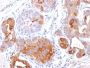

This antibody recognizes a protein of 15 kDa, identified as Gross cystic disease fluid protein 15 (GCDFP-15). It is a major protein component of benign breast gross cysts. It is a known marker of breast cancer, as it is found in approximately 50% of all breast cancer specimens. GCDFP-15, also known as PIP, for prolactin inducible protein, is a prolactin and androgen controlled protein. This antibody is useful in the identification of metastatic breast carcinoma, or fluid analysis.Primary antibodies are available purified, or with a selection of fluorescent CF® Dyes and other labels. CF® Dyes offer exceptional brightness and photostability. Note: Conjugates of blue fluorescent dyes like CF®405S and CF®405M are not recommended for detecting low abundance targets, because blue dyes have lower fluorescence and can give higher non-specific background than other dye colors.

Positive Control

HepG2 Cells. Breast or Pancreas.

IHC, FFPE (verified)|WB (verified)

IHC (FFPE) (verified)|WB (verified)

Higher concentration may be required for direct detection using primary antibody conjugates than for indirect detection with secondary antibody|Immunofluorescence: 0.5-1 ug/mL|Immunohistology (formalin): 0.5-1 ug/mL|Staining of formalin-fixed tissues is enhanced by boiling tissue sections in 10 mM Tris buffer with1 mM EDTA|Flow Cytometry 0.5-1 ug/million cells/0.1 mL|Western blotting 0.5-1 ug/mL|Optimal dilution for a specific application should be determined by user